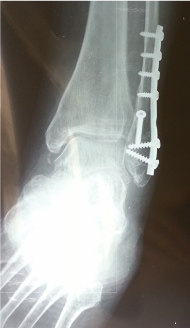

During screw placement, proximal bicortical screws Number 4 up to the most proximal inserted screw, had satisfactory fixation grip strength. Distal unicortical screws Number 1 to Number 3 had reduced fixation grip strength in 147 (45%) of the 330 placed screws. The first screw had reduced fixation grip strength in 49 (36%), the second in 86 (63%), and the third in 12 (21%) of screws placed (Table 1). The loss of strength during screws positioning evaluated with the two fingers technique. The percentage of stripped screws increased in older patients with poor bone stock quality. However, this is not evident in intraoperative or postoperative radiographs (Figure 2).

Figure 2: Post-operative AP radiograph of the ankle one month after surgery, with reduced fixation grip strength intraoperatively position 2 (S2). The reduced fixation grip is not visible. View Figure 2